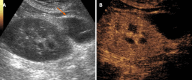

Kidney transplantation (KT) is an effective treatment for end-stage renal disease. Despite their rate has reduced over time, post-transplant complications still represent a major clinical problem because of the associated risk of graft failure and loss. Thus, post-KT complications should be diagnosed and treated promptly. Imaging plays a pivotal role in this setting. Grayscale ultrasound (US) with color Doppler analysis is the first-line imaging modality for assessing complications, although many findings lack specificity. When performed by experienced operators, contrast-enhanced US (CEUS) has been advocated as a safe and fast tool to improve the accuracy of US. Also, when performing CEUS there is potentially no need for further imaging, such as contrast-enhanced computed tomography or magnetic resonance imaging, which are often contraindicated in recipients with impaired renal function. This technique is also portable to patients' bedside, thus having the potential of maximizing the cost-effectiveness of the whole diagnostic process. Finally, the use of blood-pool contrast agents allows translating information on graft microvasculature into time-intensity curves, and in turn quantitative perfusion indexes. Quantitative analysis is under evaluation as a tool to diagnose rejection or other causes of graft dysfunction. In this paper, we review and illustrate the indications to CEUS in the post-KT setting, as well as the main CEUS findings that can help establishing the diagnosis and planning the most adequate treatment.